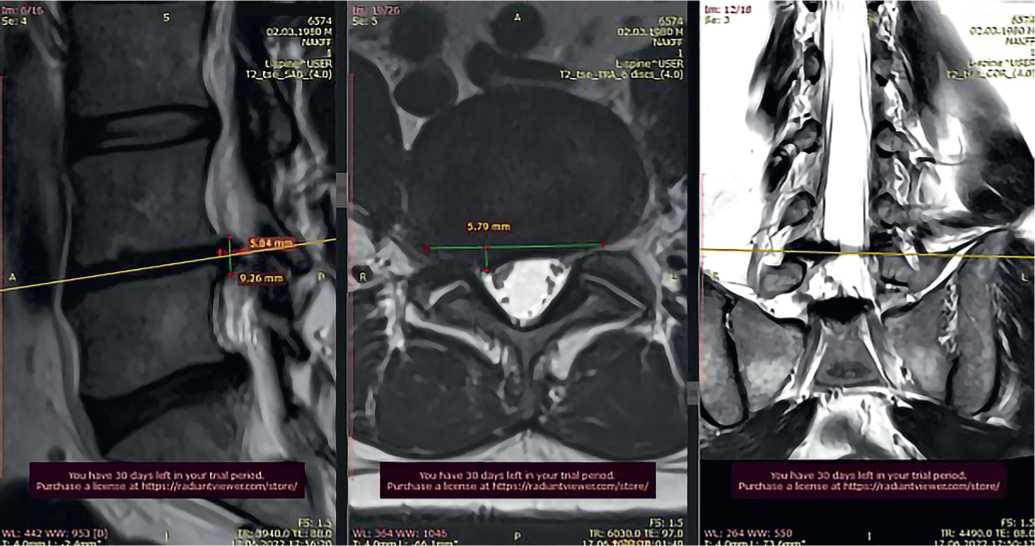

Пациент К., 41 года, обратился в Центр китайской медицины «Синь-я-Чжу» 22.12.2021 с жалобами на постоянную острую боль в пояснице с иррадиацией в правую нижнюю конечность, онемение пальцев стопы; движения ограничены — не может наклоняться, трудно сидеть. Ранее обращался к остеопатам и массажистам — без эффекта. Данные магнитно-резонансной томографии (МРТ) — грыжи дисков L4–L5, выступающая в спиномозговой канал на 13 мм, ширина секвестра 14 мм, каудальное распространение на 18 мм (рис. 2). Консультация нейрохирурга — рекомендовано оперативное лечение.

Рис. 2. Исходная магнитно-резонансная томограмма пациента К. при обращении 22.12.2021: A) саггитальный срез, B) аксиальный срез на уровне межпозвонкового диска L4-L5, C) фронтальный срез

Fig. 2. Initial magnetic resonance imaging of patient K. upon presentation on 22.12.2021: A) sagittal section, B) axial section at the level of the intervertebral disc L4-L5, C) frontal section